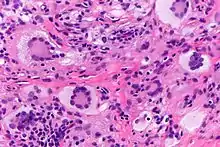

Las células gigantes de Touton, siendo células gigantes multinucleadas, puede ser distinguidas por la presencia de varios núcleos en un patrón distintivo. Contienen un anillo de núcleos que rodean un citoplasma homogéneo central, mientras que el citoplasma que rodea a los núcleos es espumoso.[4][5] El citoplasma rodeado por los núcleos ha sido descritos como anfófilo y eosinofílico, mientras que el citoplasma de la periferia celular tiene un aspecto pálido y espumoso.[6]